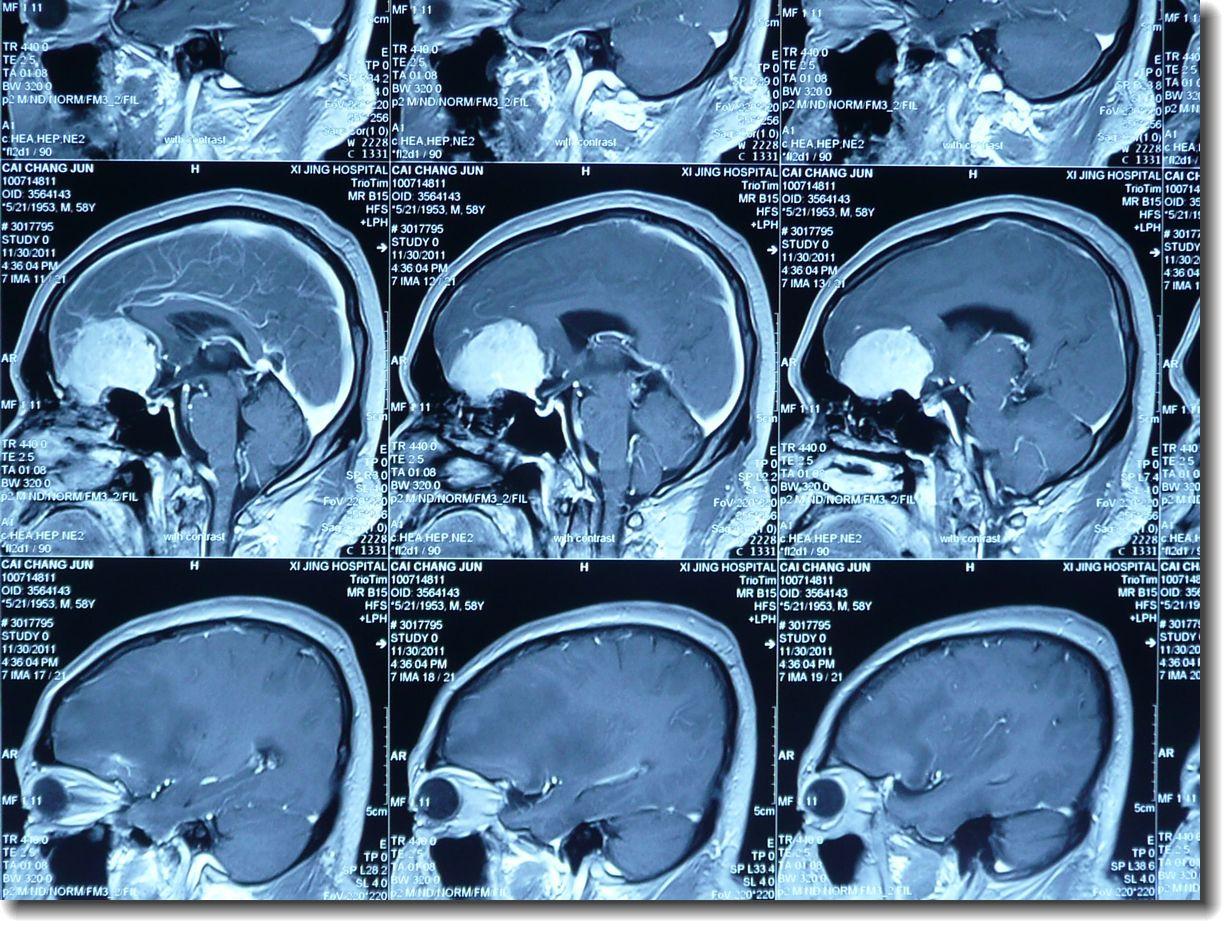

3、头部MRI(磁共振成像)检查

T1WI为等或略低信号,T2WI为等或略高信号。强化扫描显示,多数病灶鞍区、颈内动脉周围及大脑中动脉均有明显强化。该肿瘤附在蝶窦平台,视交叉沟和硬脑膜鞍结节上,且基底较宽。鼠尾征有特征性,可见于硬脑膜。